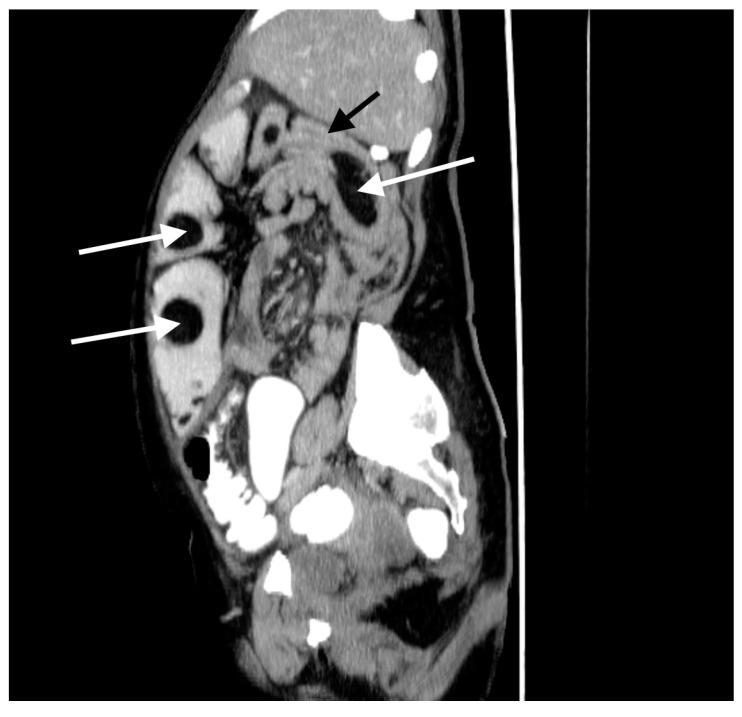

空肠憩室病和空肠脂肪瘤病是罕见病症。通常无症状,但在某些情况下可能引发严重并发症。肠套叠在成年人中并不常见,但如果能迅速诊断,可通过手术治疗,通常预后良好。

我们报告一例60岁女性患者,有慢性营养不良和贫血病史,主诉急性腹痛、呕吐和腹泻。腹部增强计算机断层扫描(CT)显示肠套叠、多个巨大空肠憩室和多个脂肪瘤。患者接受了紧急手术,但由于病情严重程度无法进行根治性治疗。一个月后,因脂肪瘤导致回肠造口梗阻,需要再次手术。患者因营养不良和并发的代谢紊乱病情恶化,最终死亡。